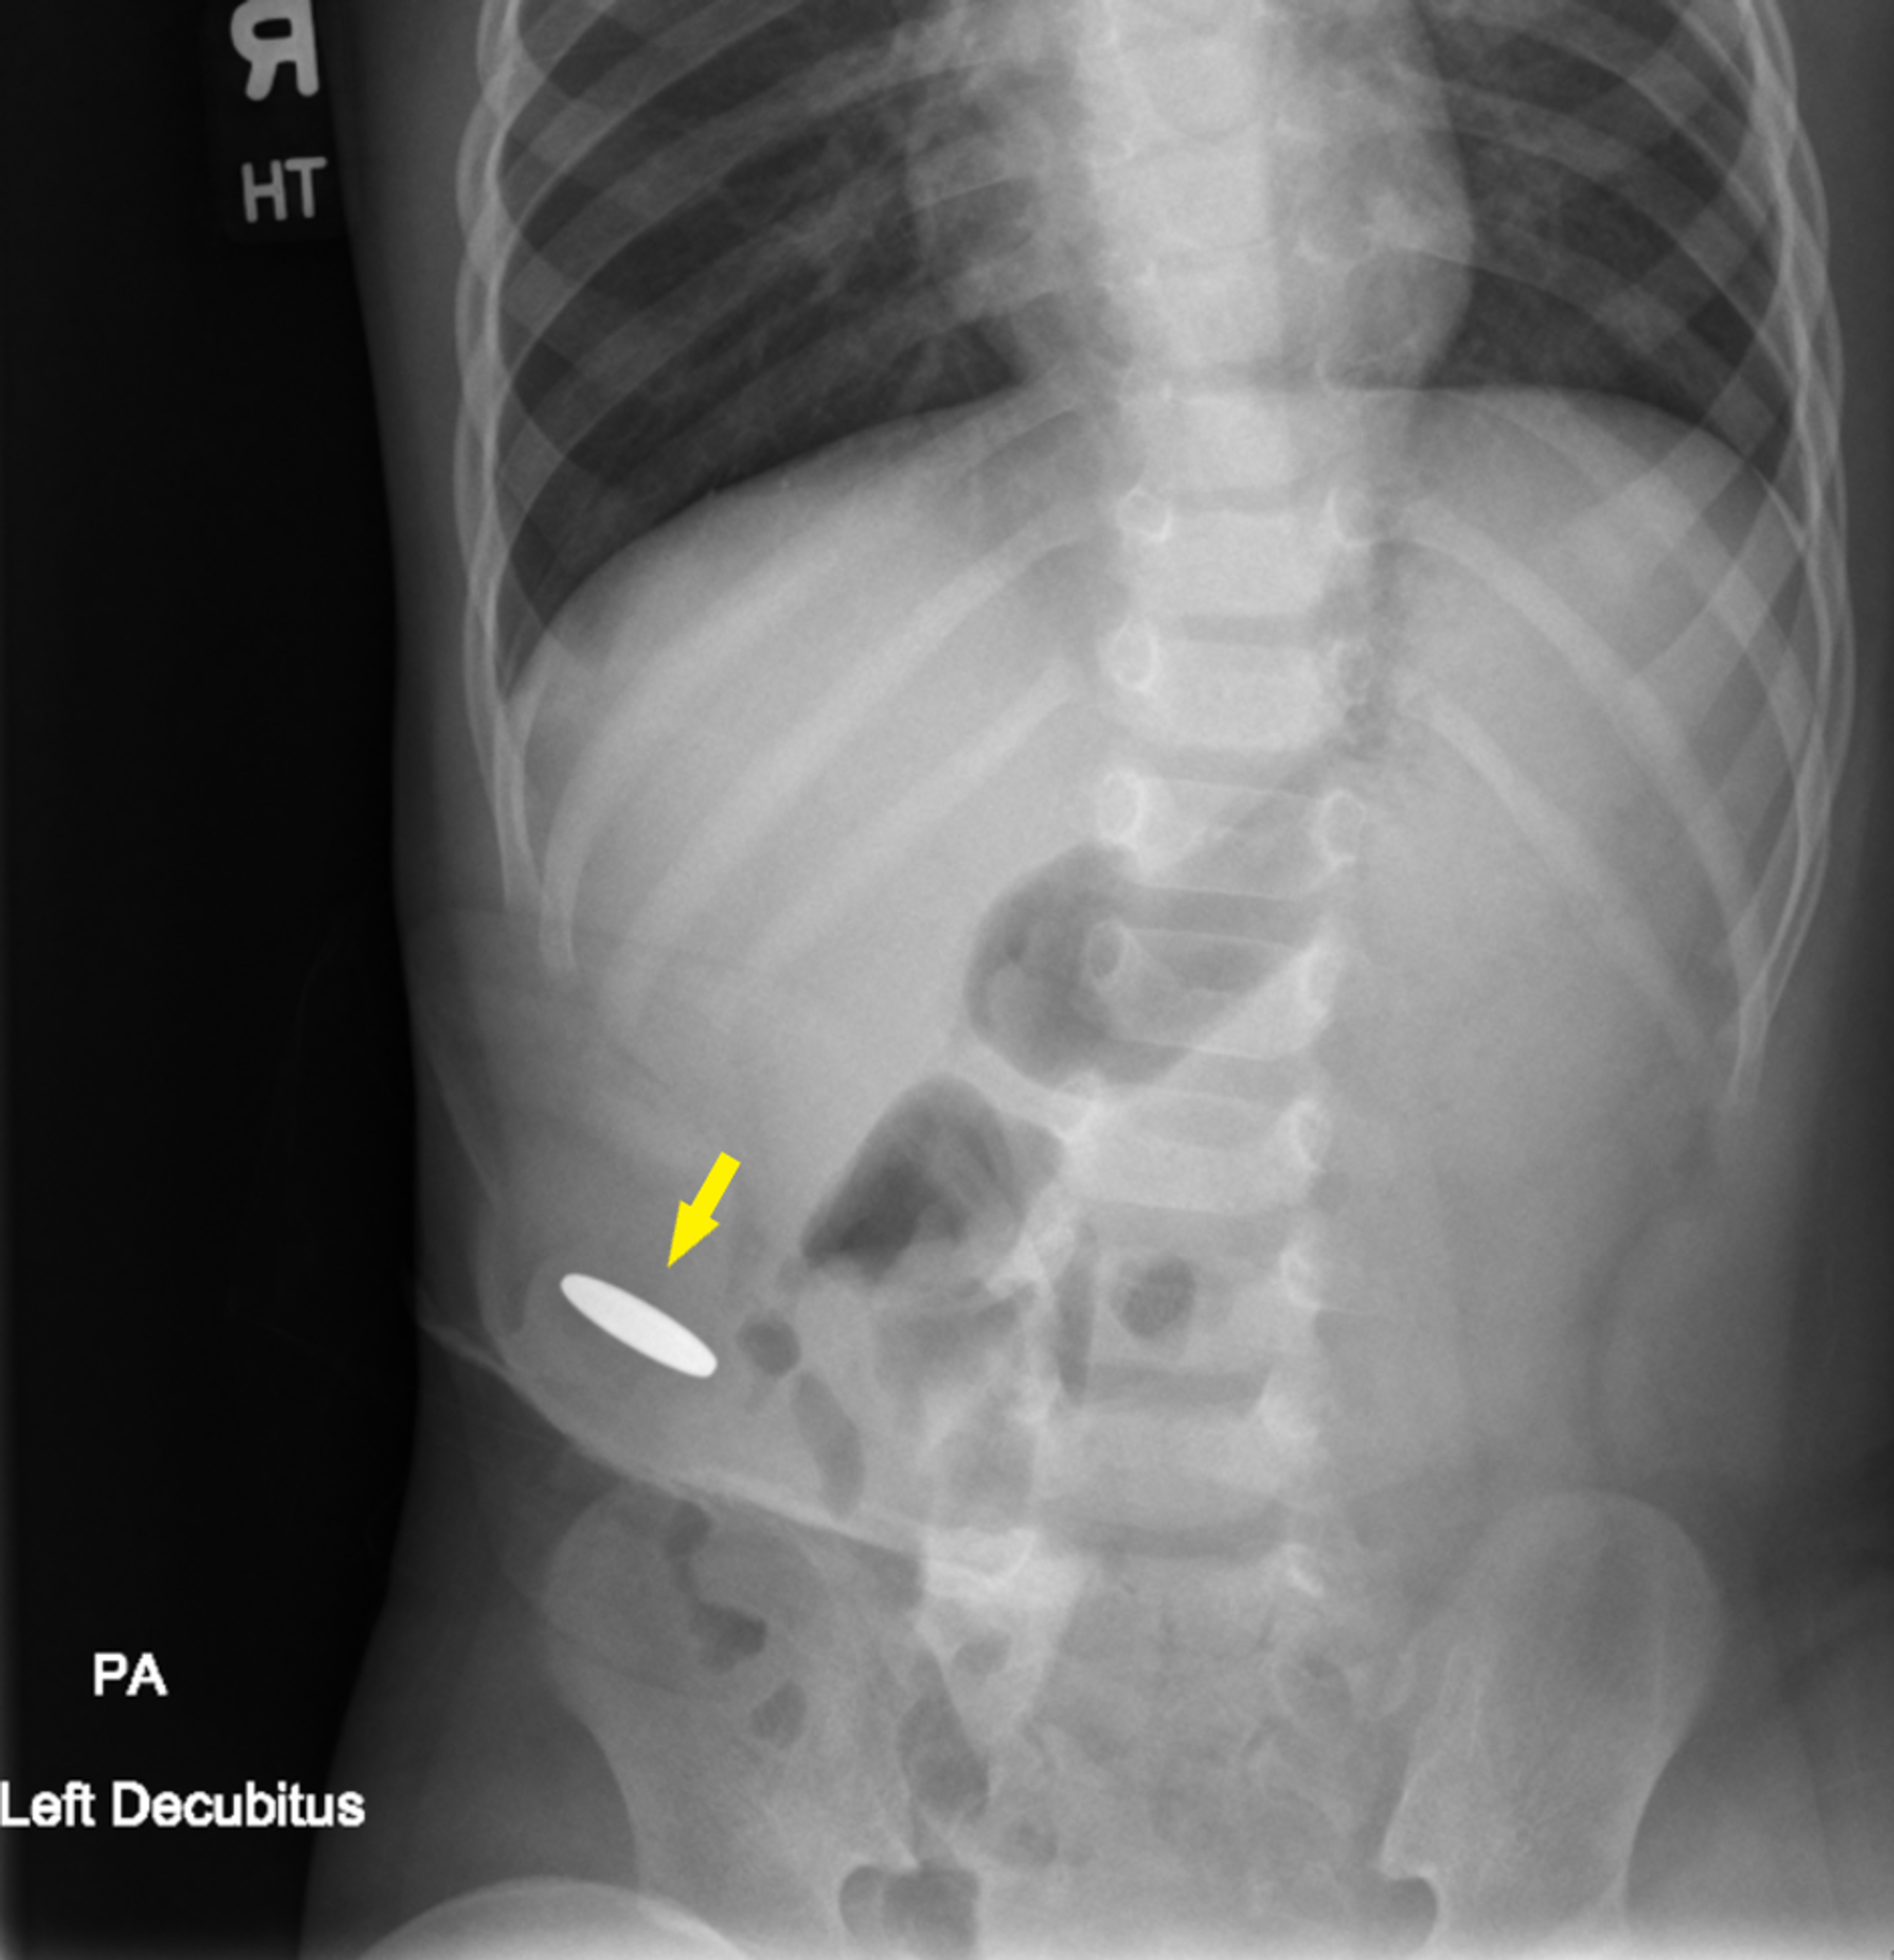

Xray of abdomen demonstrating foreign object in left midabdomen. A No Radiopaque Foreign Body radiopaque foreign bodies pose potential health risks and discomfort when lodged in the body. It is difficult to confirm their. However, all foreign bodies are. imaging is especially necessary following the removal of multiple foreign body pieces or when wound exploration is not possible. whenever a foreign body was localized, its length and depth beneath the. . No Radiopaque Foreign Body.